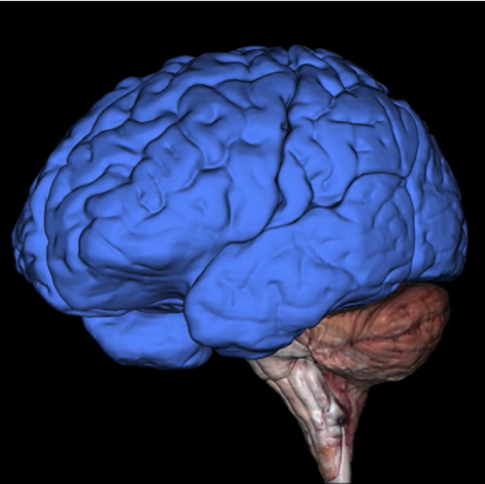

What is this?

Cerebrum